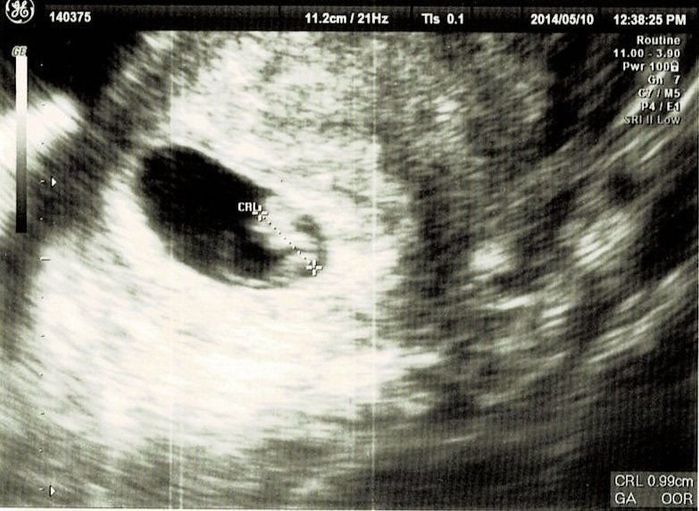

妊娠10週目エコー写真

職場の上司にはこの時点で報告しておきました。「もし、妊娠が継続しなかったら……」ということも考えたのですが、早く伝えたほうが会社にも迷惑がかからないだろうと考えました。このとき、初めて心拍が確認できました。診察後産院の受付に行くと、「赤ちゃんに会える日を楽しみにしています」と書かれたメッセージカードを頂きました。中を開くとエコー写真が。大感激して、今でも大切に取ってあります。